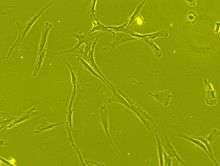

Mesenchymal stem cells are characterized morphologically by a small cell body with a few cell processes that are long and thin. The cell body contains a large, round nucleus with a prominent nucleolus, which is surrounded by finely dispersed chromatin particles, giving the nucleus a clear appearance. The remainder of the cell body contains a small amount of Golgi apparatus, rough endoplasmic reticulum, mitochondria and polyribosomes. The cells, which are long and thin, are widely dispersed and the adjacent extracellular matrix is populated by a few reticular fibrils but is devoid of the other types of collagen fibrils.[18][19]

The International Society for Cellular Therapy (ISCT) has proposed a set of standards to define MSCs. A cell can be classified as an MSC if it shows plastic adherent properties under normal culture conditions and has a fibroblast-like morphology. In fact, some argue that MSCs and fibroblasts are functionally identical.[20] Furthermore, MSCs can undergo osteogenic, adipogenic and chondrogenic differentiation ex-vivo. The cultured MSCs also express on their surface CD73, CD90 and CD105, while lacking the expression of CD11b, CD14, CD19, CD34, CD45, CD79a and HLA-DR surface markers.[21]